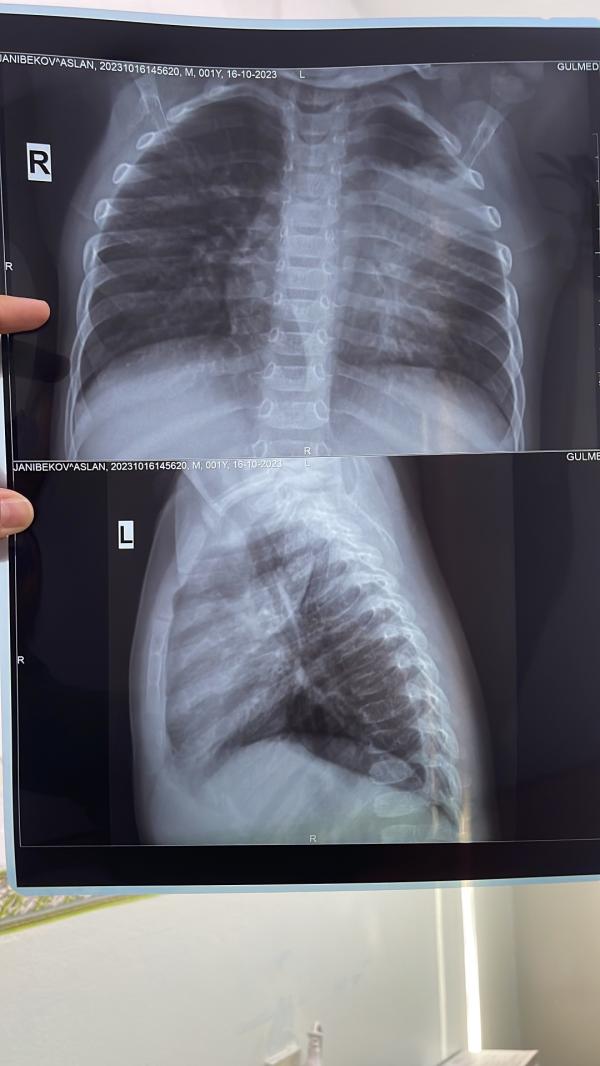

Здравствуйте дорогие, сын всё болел не могли выздороветь почти месяц, была обструкция сказали срочно сделать рентген легких, результат показал что есть какое то пятно в левой стороне, у кого нибудь было такое? 🙁 заключение точное дадут завтра